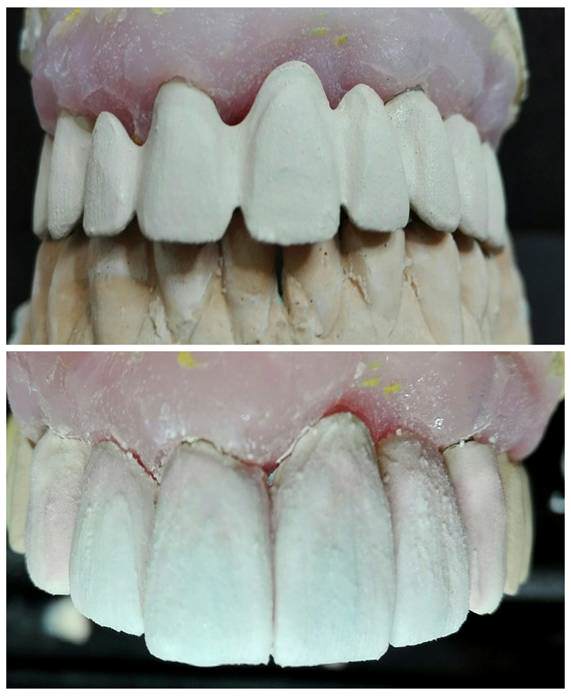

ESTRATIFICACIÓN Y PRUEBA DE BIZCOCHO

Opacamos la estructura y comenzamos la estratificación cerámica. Enviamos la prueba a clínica para valorar estética y oclusión.

![]() | ![]() |

REAJUSTES , GLASEADO Y TERMINACIÓN DE REHABILITACIÓN